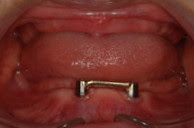

この患者さんは上下とも一本も歯がなかった方です。

下顎には、当院でインプラントを2本入れました。左右のインプラントにバーを渡し、入

れ歯の粘膜面にバーのメス型(鞘)を装着します。このようなアタッチメントという装置

を入れることによって、お食事したときも外れたりすることなく、良く噛めているそうで

す。

さらに、下の入れ歯は「金属床」と言って入れ歯の内面に金属が入ることによって強度が

増し薄く作ることができ、違和感も少なくなります。